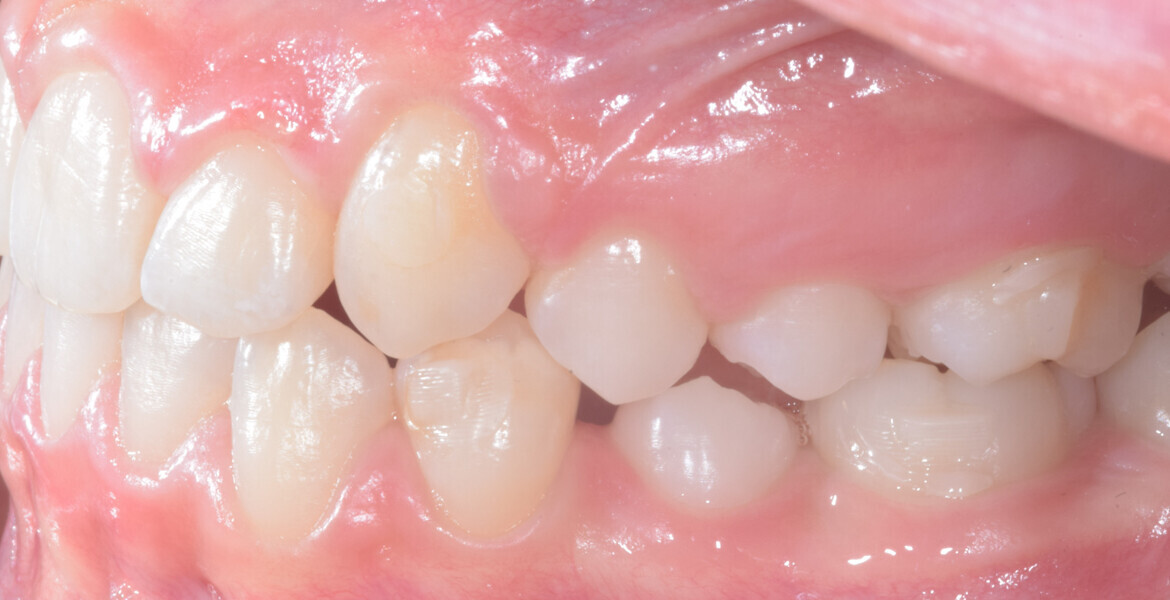

A 14-year-old female patient presented with the chief complaint of midline deviation and dental crowding in both arches. Facial analysis showed a hypodivergent growth pattern, a normal nasolabial angle, a harmonious profile and proper chin projection. Clinical examination revealed a Class III skeletal relationship (ANB = 0°) and Class I molar relationship. The maxillary right canine was absent, and this had led to space loss and mesial drift of posterior teeth on the right side, resulting in a slight Class II molar relationship. The maxillary left canine had erupted in a high position. The mandibular arch displayed crowding despite the agenesis of the right second premolar and the persistence of the primary molar (Figs. 3–11). The radiograph showed the probably premature loss of the maxillary right primary canine and consequently impacted maxillary right permanent canine, and the agenesis of the mandibular right second premolar and the mandibular right third molar (Fig. 12).

Fig. 3

Fig. 4

Fig. 5

Fig. 6